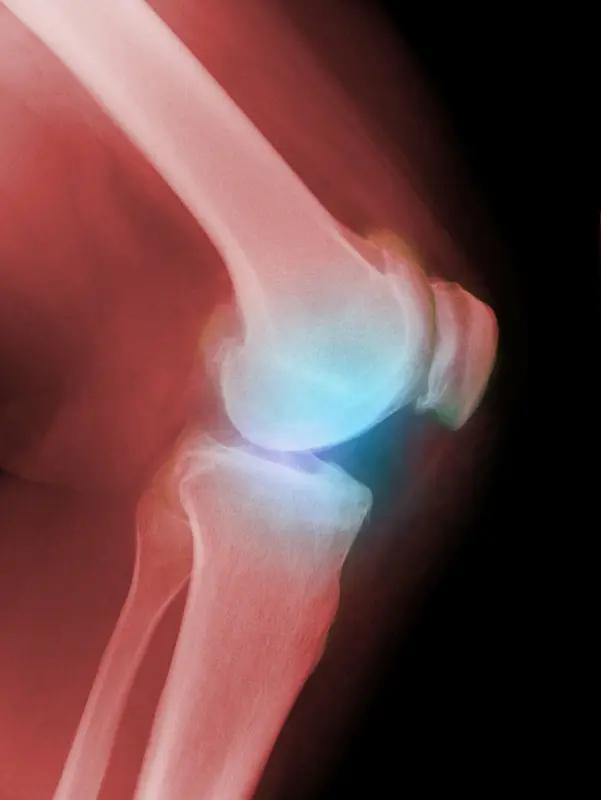

事情是这样的:明天我要去医院给膝盖打玻璃酸钠。